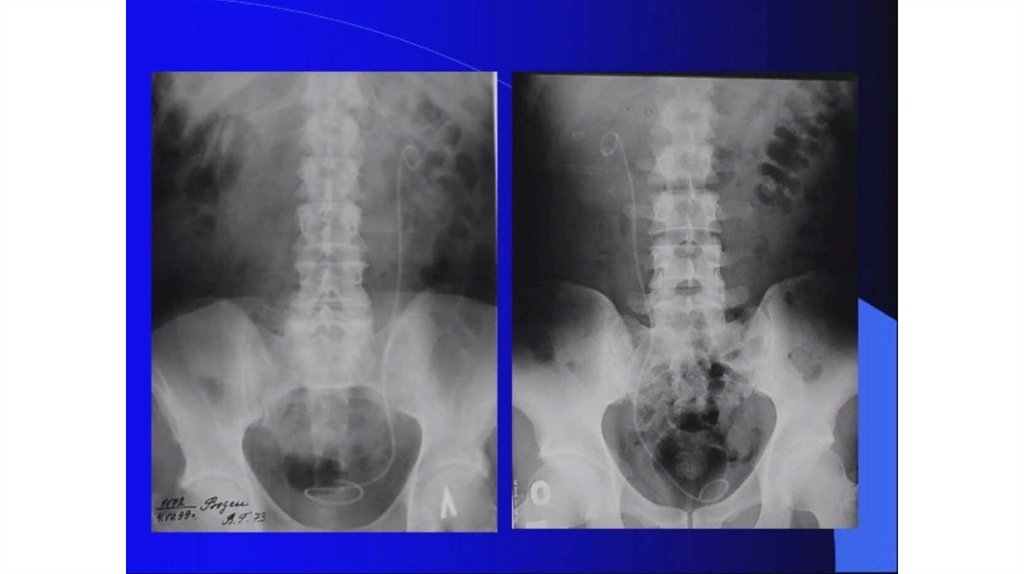

Мочекаменная болезнь. Мочекаменная болезнь и беременность

Мочекаменная болезнь